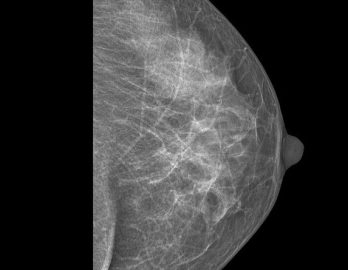

Sabemos que visitar un centro médico a veces genera nervios. Por eso, hemos creado un ambiente cálido, moderno y 100% seguro para ti. Desde nuestra cómoda sala de espera hasta nuestras áreas de ecografía, mamografía y rayos X, cada rincón está equipado con tecnología de última generación y diseñado para que te sientas en confianza.